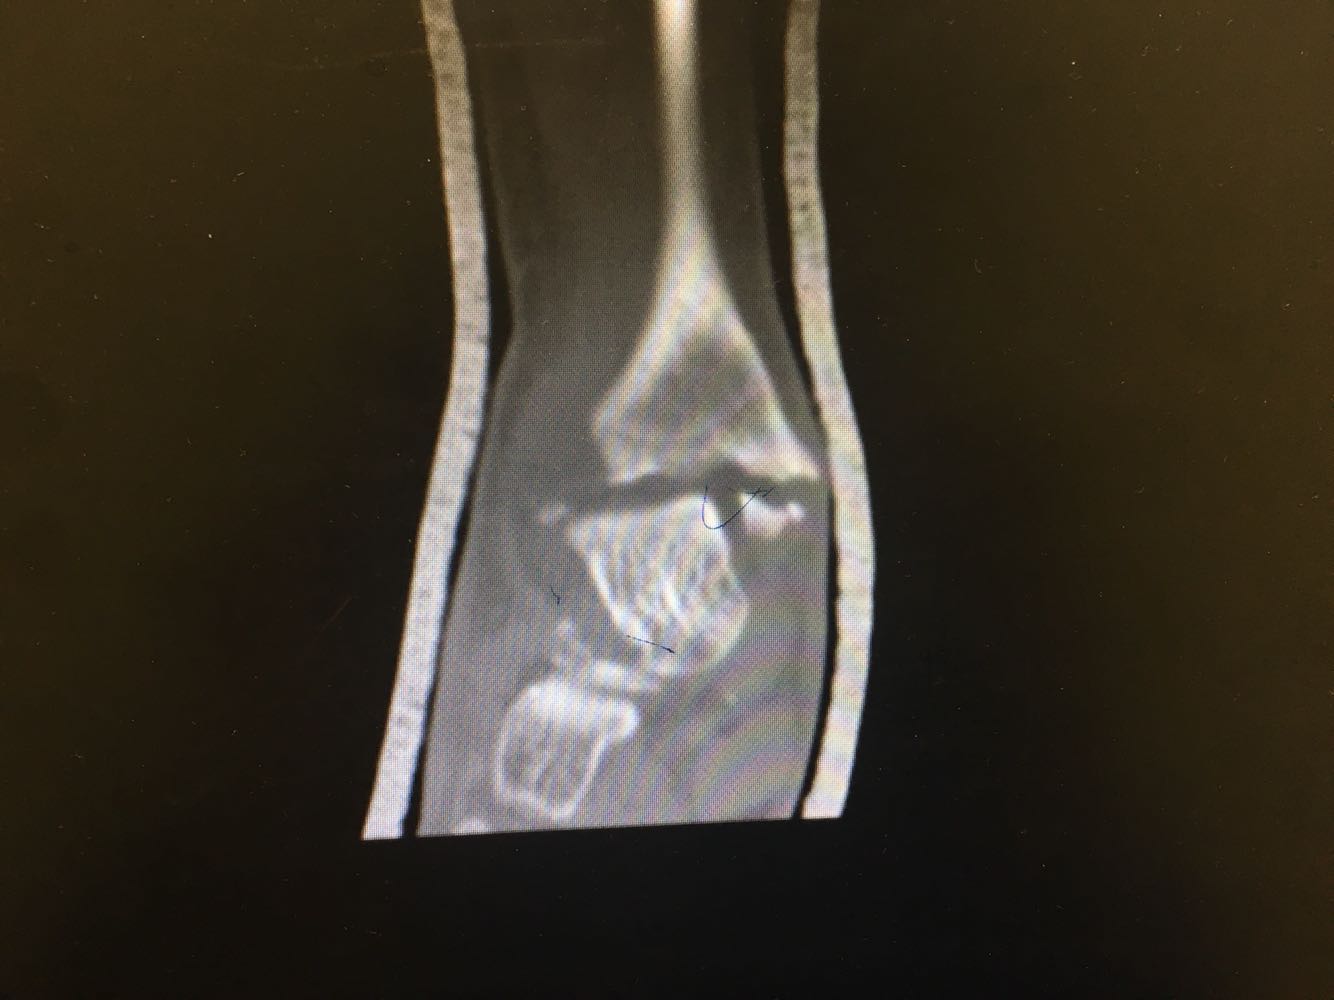

患者,男,54岁。 主诉:外伤致右踝疼痛伴活动受限2天 现病史:患者于2天前不慎扭伤致右踝疼痛,伴活动受限,否认头晕头痛、恶心呕吐等不适,就近医院就诊,查X片示:右踝骨折,予石膏外固定,现为进一步诊治收治入院,发病以来,神清,精神可,胃纳夜眠可,二便无殊,体重无明显变化。

查体:右踝压痛,活动受限,无淤斑淤点,未见皮肤破损,足趾感觉及运动良好。 辅检:右踝部CT

诊断:右侧踝部闭合性骨折 治疗:完善术前检查后行手术内固定